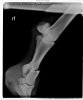

Жеребец. Винтовой перелом путовой кости на ЛЗ почти по всей её длине, внизу перелома смещение 5 отломков.

Отрада отказалась, практически все веты, кому звонили - как видели рентгены и слышали описание, рекомендовали усыпить.

Брался НВ - остеосинтез на пластины и штифты. перегипсовка каждые определенные периоды. Наложение гипса при таких переломах отличается на передней ноге получен перелом или задней. На задней сложнее. Нужен наркоз каждый раз.

Еще один ветеринар (спасибо ему!) сказал, что можно побороться. Приехал, наложили гипс с учетом особенностей такого процесса на заднюю ногу.

НВ давал прогноз осторожный. абсолютно все, даже при условии того, что конь не загнется от ХОБЛ, что не схватит ламинит и т.д. предупреждали о газонокосилке в итоге.

Стоял с гипсом 2,5 месяца, постоянные рентгены, жрал кучу всего. Гипс он как-то так продавил пяткой или что еще сделал, но получился, как костыль, на который он мог опираться и как-то даже перемещался по деннику. Сразу научился ложиться, вытягивая ногу и также вставать. Он сразу хотел жить и делал всё от него зависящее. Вот в этот период у него было отличное дыхание, что вообще никто не может объяснить.

Делающие рентгены ветеринары (Отрада, Эквимедика) говорили, что его случай противоречит медицинской практике и опыту. И что это магия и что ни в коем случае никаких перегипсовок, пока вот этот гипс вопреки всему работает. не нужно трогать.